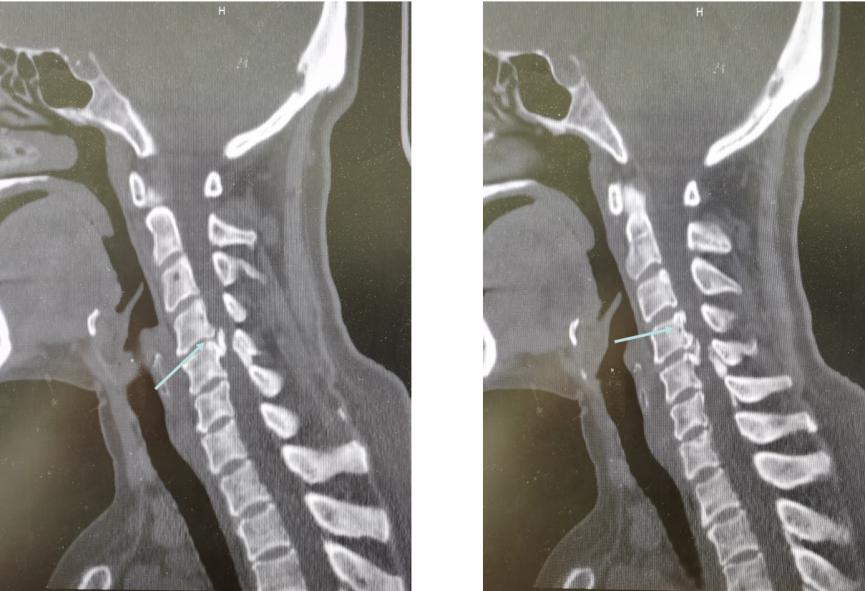

接诊了黄女士后,我为她做了详细的查体,并建议进行颈部的影像学检查。综合各项检查结果发现,原来是黄女士的颈椎出现了问题,她之所以出现这些症状是由于颈椎间盘突出造成了神经根压迫,为神经根型颈椎病。而且黄女士的情况比较严重,多个节段都出现了颈椎间突出,包括颈3/4、颈4/5、颈5/6。此外,还有后纵韧带骨化、颈椎管狭窄。这种情况,我建议黄女士进行手术治疗,将突出的椎间盘髓核切掉,并给神经充分减压。

术前CT